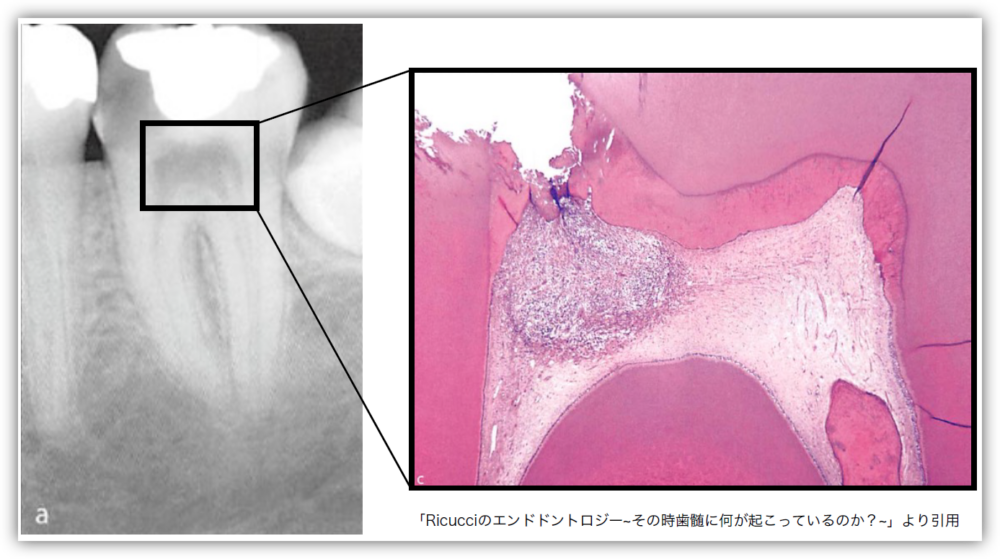

歯の中心にある組織「歯髄(しずい)」は、単に“神経”という意味だけではなく、血管・リンパ管などの生きた組織が含まれています。この歯髄があることで、虫歯の進行時に「冷たいものがしみる」などのサインが出たり、免疫機能として感染に抵抗したりする役割を果たしています。

「歯髄保存治療」は、むやみに歯髄を取り除かず、できる限り歯の内部の神経や血管を残すことを目標にした治療です。歯髄を残すことで、歯の強度維持や本来の生理的機能を保つことが期待できます。

ただし「闇雲に歯髄を残す」ことが必ずしも正解ではありません。無理に残した結果、歯髄の壊死や慢性炎症を招き、将来的に治療が難しくなる可能性もあるため、適応と判断が不可欠です。

小さく露出した歯髄の状態(健康か炎症があるか)を見極めます。